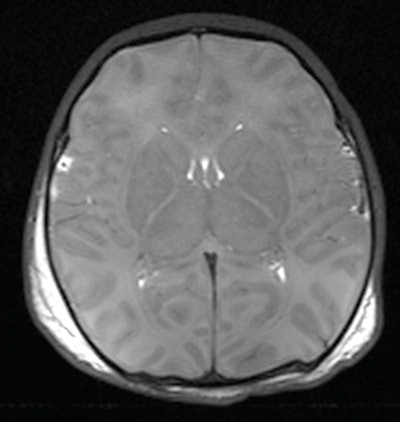

Because postmortem MRI has high accuracy in detecting congenital abnormalities and other major brain pathology in fetuses and children, it may be used as a screening tool for detecting significant brain abnormality, noted the Magnetic Resonance Imaging Autopsy Study (MaRIAS) group, which is led by Dr. Andrew Taylor, professor of pediatric cardiac radiology, and Dr. Neil Sebire, professor of pediatric pathology, both from UCL.

MRI is a particularly good, noninvasive, high spatial resolution exam that gives excellent image contrast between cerebrospinal fluid and brain tissue, thus providing distinct anatomical details. Postmortem MRI, when used in conjunction with other ancillary investigations, has recently been shown to have a high diagnostic accuracy rate for cause of death or main diagnosis compared with traditional autopsy in fetuses, stillbirths, and children.

Cerebral malformations | 88.4% | 95.2% |

Major intracranial bleeds | 100% | 99.1% |

Overall brain pathology | 87.5% | 74.1% |